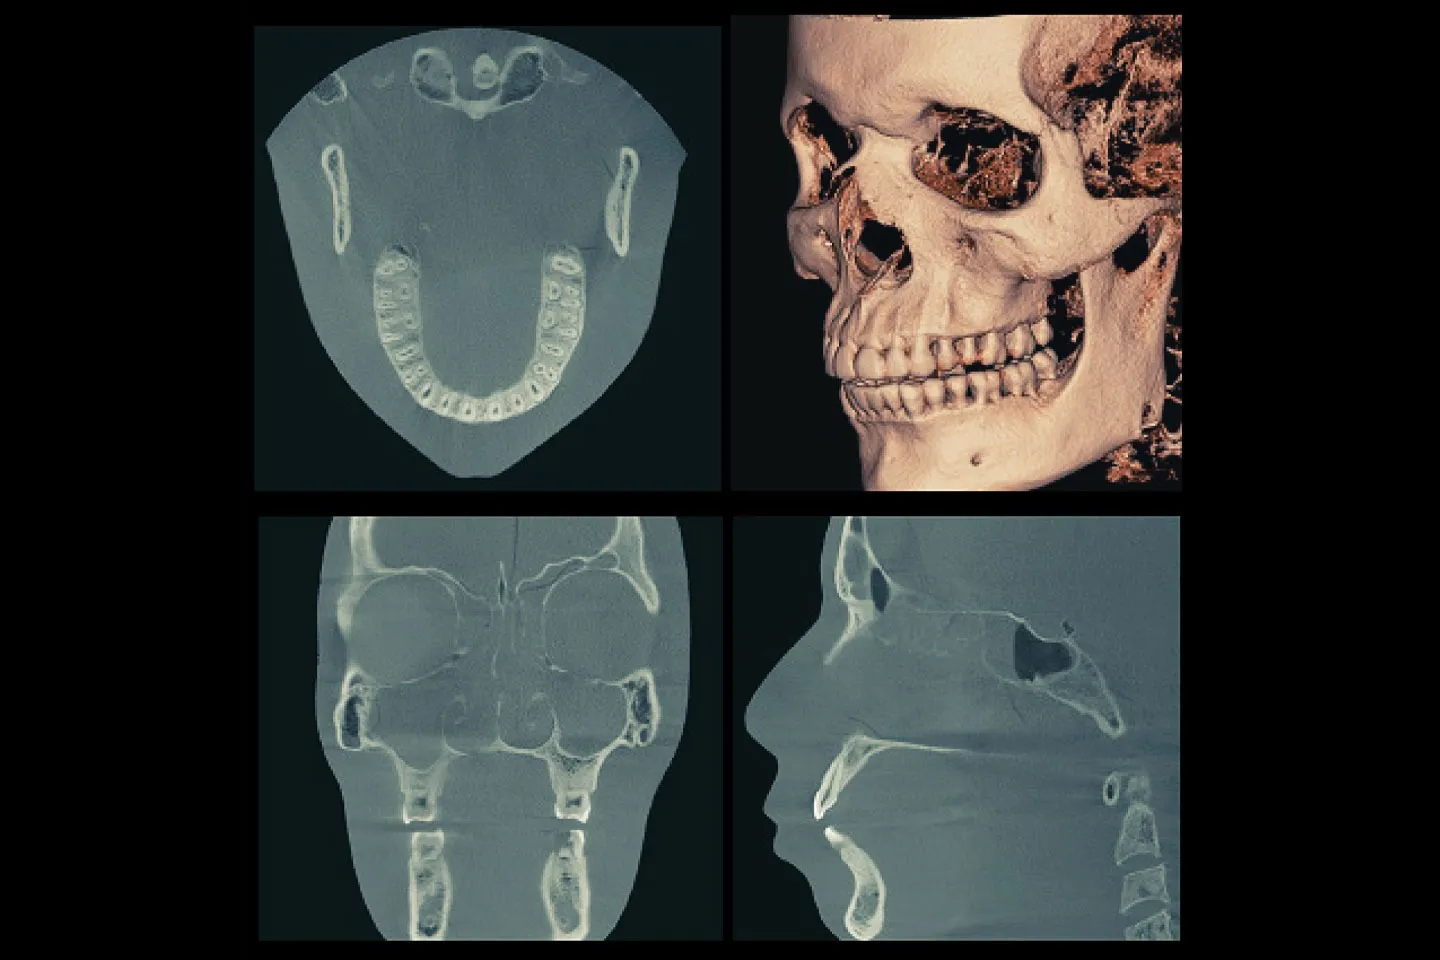

2. 精密診断資料採り